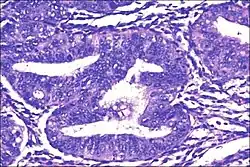

Micrograph showing simple endometrial hyperplasia, where the gland-to-stroma ratio is preserved but the glands have an irregular shape and/or are dilated. Endometrial biopsy. H&E stain. | |

Like other hyperplastic disorders, endometrial hyperplasia initially represents a physiological response of endometrial tissue to the growth-promoting actions of estrogen. However, the gland-forming cells of a hyperplastic endometrium may also undergo changes over time which predispose them to cancerous transformation. Several histopathology subtypes of endometrial hyperplasia are recognisable to the pathologist, with different therapeutic and prognostic implications.[4]

- Endometrial hyperplasia (simple or complex) - Irregularity and cystic expansion of glands (simple) or crowding and budding of glands (complex) without worrisome changes in the appearance of individual gland cells. In one study, 1.6% of patients diagnosed with these abnormalities eventually developed endometrial cancer.[7]